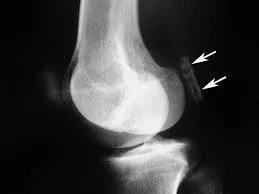

文章插图

它的直径不足1.3厘米 , 是在我们灵长类祖先身体上发现的 , 它被称为“骨骼阑尾” , 因为它的存在是毫无意义的 。 所以在古猿向人类发展的进程中 , 豆骨已经消失 。

然而研究人员分析了过去150多年进行的2.1万多项科学研究 , 发现目前豆骨在人体存在的概率是100年前的3倍 , 全球40%的人都长有豆骨 。

不过 , 豆骨它的存在可能并不总是被X光或CT扫描所发现 。 例如 , 一项针对中国人群的研究报告说 , 57.9%的豆骨在X光片上看不到 。